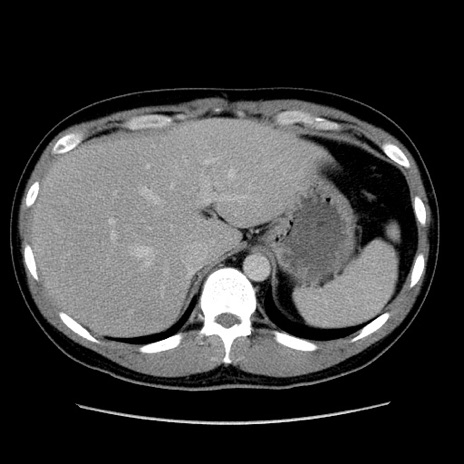

症例4(横断像)

【症例】30歳代男性

【主訴】腹痛、嘔吐

【現病歴】昨晩から突然の腹痛あり、その後嘔吐、軟便も出現。腹痛が改善しないため救急搬送となる。2日前にしめ鯖の食事歴あり。

【身体所見】意識清明、苦悶様、BP 135/90mmHg、BT 35.7℃、腹部:平坦、やや硬、心窩部〜臍部に自発痛、圧痛あり、筋性防御+、反跳痛-

【データ】WBC 8100、CRP 0.57